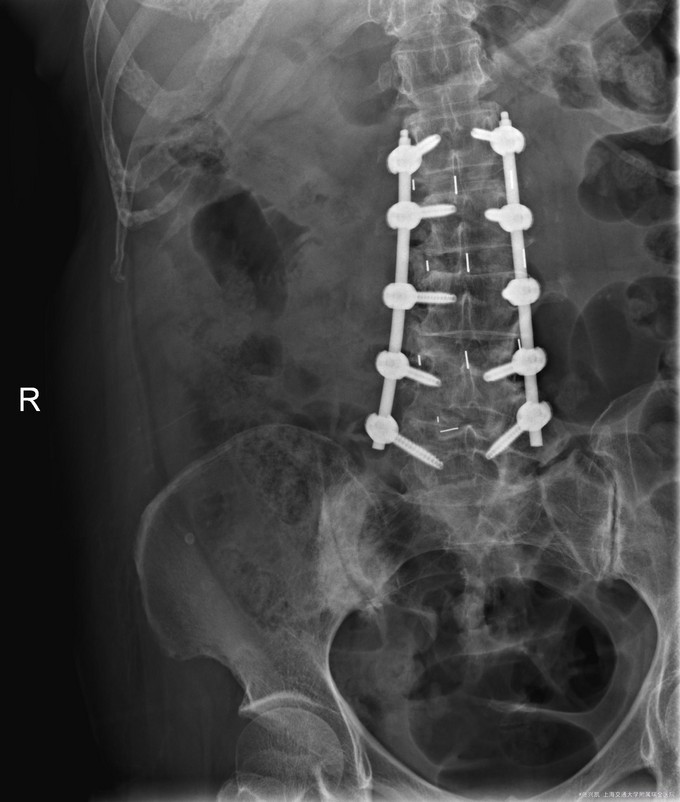

主诉:双下肢麻木7年,腰部酸痛无力 现病史:女性患者,70岁,患者诉腰背无力十几年,约于7年前无明显诱因下出现下肢麻木,站立位加重。后出现腰臀部僵硬,弓背加重,行走距离较短, 不足百米,几年前外院检查诊断为腰椎管狭窄,具体不详。

查体:侧弯畸形,右臀部及右下肢麻木疼痛,腰部活动受限,难以站立。右侧支腿抬高试验50°。双下肢肌力肌张力可。 辅助检查: 磁共振:L1-5,L5-S1腰椎椎间盘突出,腰椎退变,腰椎侧弯

诊断: 腰椎侧弯,腰椎间盘突出 治疗:1期微创侧路椎体融合术+2期 微创后路经皮内固定术

患者侧路微创术后神经压迫症状减轻,腰椎矢状位及冠状位腰椎力线得到改善,戴支具术后可早期下床活动,术后2周后行后路固定手术。